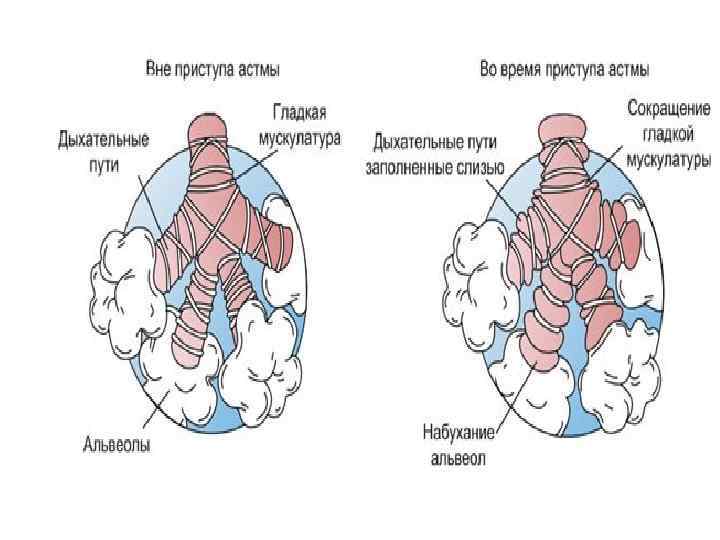

Бронхиальная астма хроническое воспалительное заболевание бронхов с периодически возникающими приступами затрудненного дыхания или удушья в результате распространенной бронхиальной обструкции, обусловленной острым бронхоспазмом, отеком стенки бронхов, гиперсекрецией слизи.